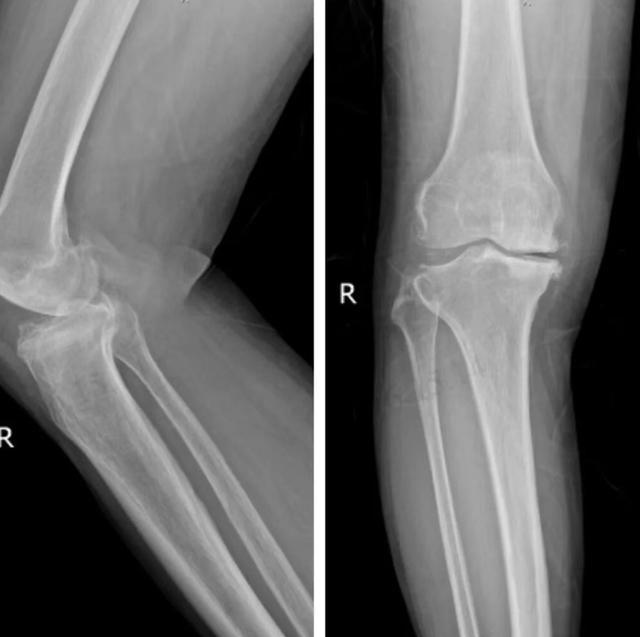

(▲术前膝关节影像片,可见右膝关节退变严重,内侧关节间隙明显狭窄,下肢全长片亦可见右膝关节明显内翻畸形)

抱着试一试的想法,尹阿姨找到了刘洪主任。刘洪耐心问诊、细致查体,结合影像学检查,确诊尹阿姨为双侧膝关节骨性关节病(右侧偏重)。